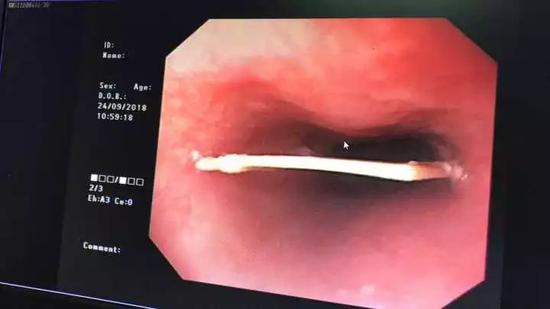

通过无痛胃镜一看,小龙的食道里有个3厘米的鸭骨头卡着,并且已有轻微划伤出血,最后在医护人员的努力下,骨头被安全取出。

不过“这么大的一块骨头,我到底是怎么吃进去的呀!”看着从食道内取得的鸭骨头,小龙始终不敢相信,后怕地说道:“以前我一直以为这种事只会发生在老人身上,没想到,我这么年轻也会中招。”